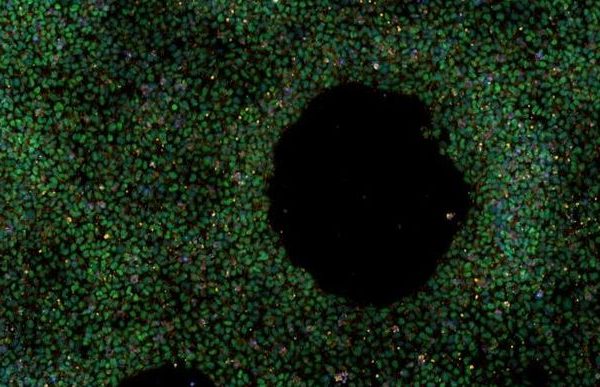

È stata creata la prima banca di cellule staminali chiamata “iPSC Platform to Model Alzheimer’s disease Risk” (IPMAR)…